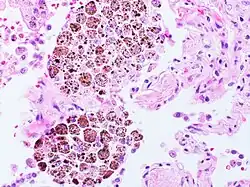

Das Hämosiderin (von altgriechisch αίμα „Blut“ [siehe Häm] und σίδηρος „Eisen“) besteht aus Bruchstücken von Ferritin, dem wichtigsten Speicherprotein für Eisen. Chemisch handelt es sich um einen wasserunlöslichen Komplex aus Eisen und verschiedenen Proteinen; der Eisenanteil beträgt etwa 37 %. Hämosiderin ist – anders als Ferritin – keine physiologische Speicherform und lässt sich nur intrazellulär auffinden, vor allem in Makrophagen. Es hat nativ eine goldgelbe Farbe, in histologischen Schnitten kann es mit der Berliner-Blau-Reaktion angefärbt und sichtbar gemacht werden.[1]

Hämosiderin entsteht besonders reichlich in Gebieten größerer Blutungen. Hämosiderinbeladene Makrophagen (sogenannte „Herzfehlerzellen“, Siderophagen) im Sputum können Hinweis auf eine Herzinsuffizienz geben. Krankheiten mit vermehrter Eisenablagerung im Organismus heißen Hämosiderosen.